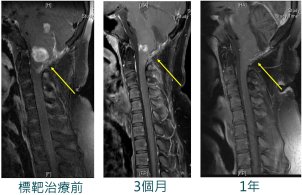

¤p»y¦b 12·³³Q¶EÂ_¥X¦³¸£·F¸~½F¡A³¡¤À¤Á°£«áÃÒ¹ê¬O§C´c©Ê«×ªº½¦½è½F¡A³N«á¥ý±Ä¨ú©w´Á°lÂܪºpµe¡C¦ý°lÂܤ@¦~´Nµo¥Í¼v¹³¤Wªº´_µo¡AÁöµM°¨¤W±µ¨ü©ñ®g¤Î¤Æ¾ÇªvÀø¡A¼v¹³¤W¸~½F¤ÏÀ³ÁÙ¬O¤£¦n¡A¥B¸£·F¥\¯à²§±`ªº¯gª¬¤]¶V¨Ó¶V©úÅã¡C¦b¸£·F¦ì¸m¤â³N¹ï¯«¸g¥~¬ìÂå®v¨Ó»¡¬D¾Ô¬Û·í¤j¡A¤â³N¦A¤Á°£ªº·ÀI¤]¸û°ª¡A¦]¦¹»P¨àµ£¦å²G¸~½F¬ìÂå®v°Q½×«á¡A¨M©w¥Î·íªì¤Á°£ªº¯f²z²Õ´¦w±Æ¦¸¥@¥N©w§Ç°ò¦]ÀË´ú¡Cµ²ªGÀË´ú¥X BRAF°ò¦]ªº²§±`¡A¸g«ØÄ³±µ¨ü¤F¤fªA¼Ð¹vÃĪ«ªvÀø¡A´XÓ¤ë«á¡A¤£¥u¼v¹³¤W¦³¶i¨B¡]¹Ï¡^¡A¸£·F¯gª¬¤]§ïµ½¤F¡C¥Ø«e¤p»y¤w¸g 16·³¤F¡AÁöµMÁÙ¦³¤@¨Ç¸~½F«á¿ò¯g¡A¤]ÁÙ¦b¨Ï¥Î¼Ð¹vÃĪ«¡A¦ý¥u»Ýnªù¶E°lÂܪvÀø¡A¥Í¬¡«~½è¤]ºâ¨}¦n¡C